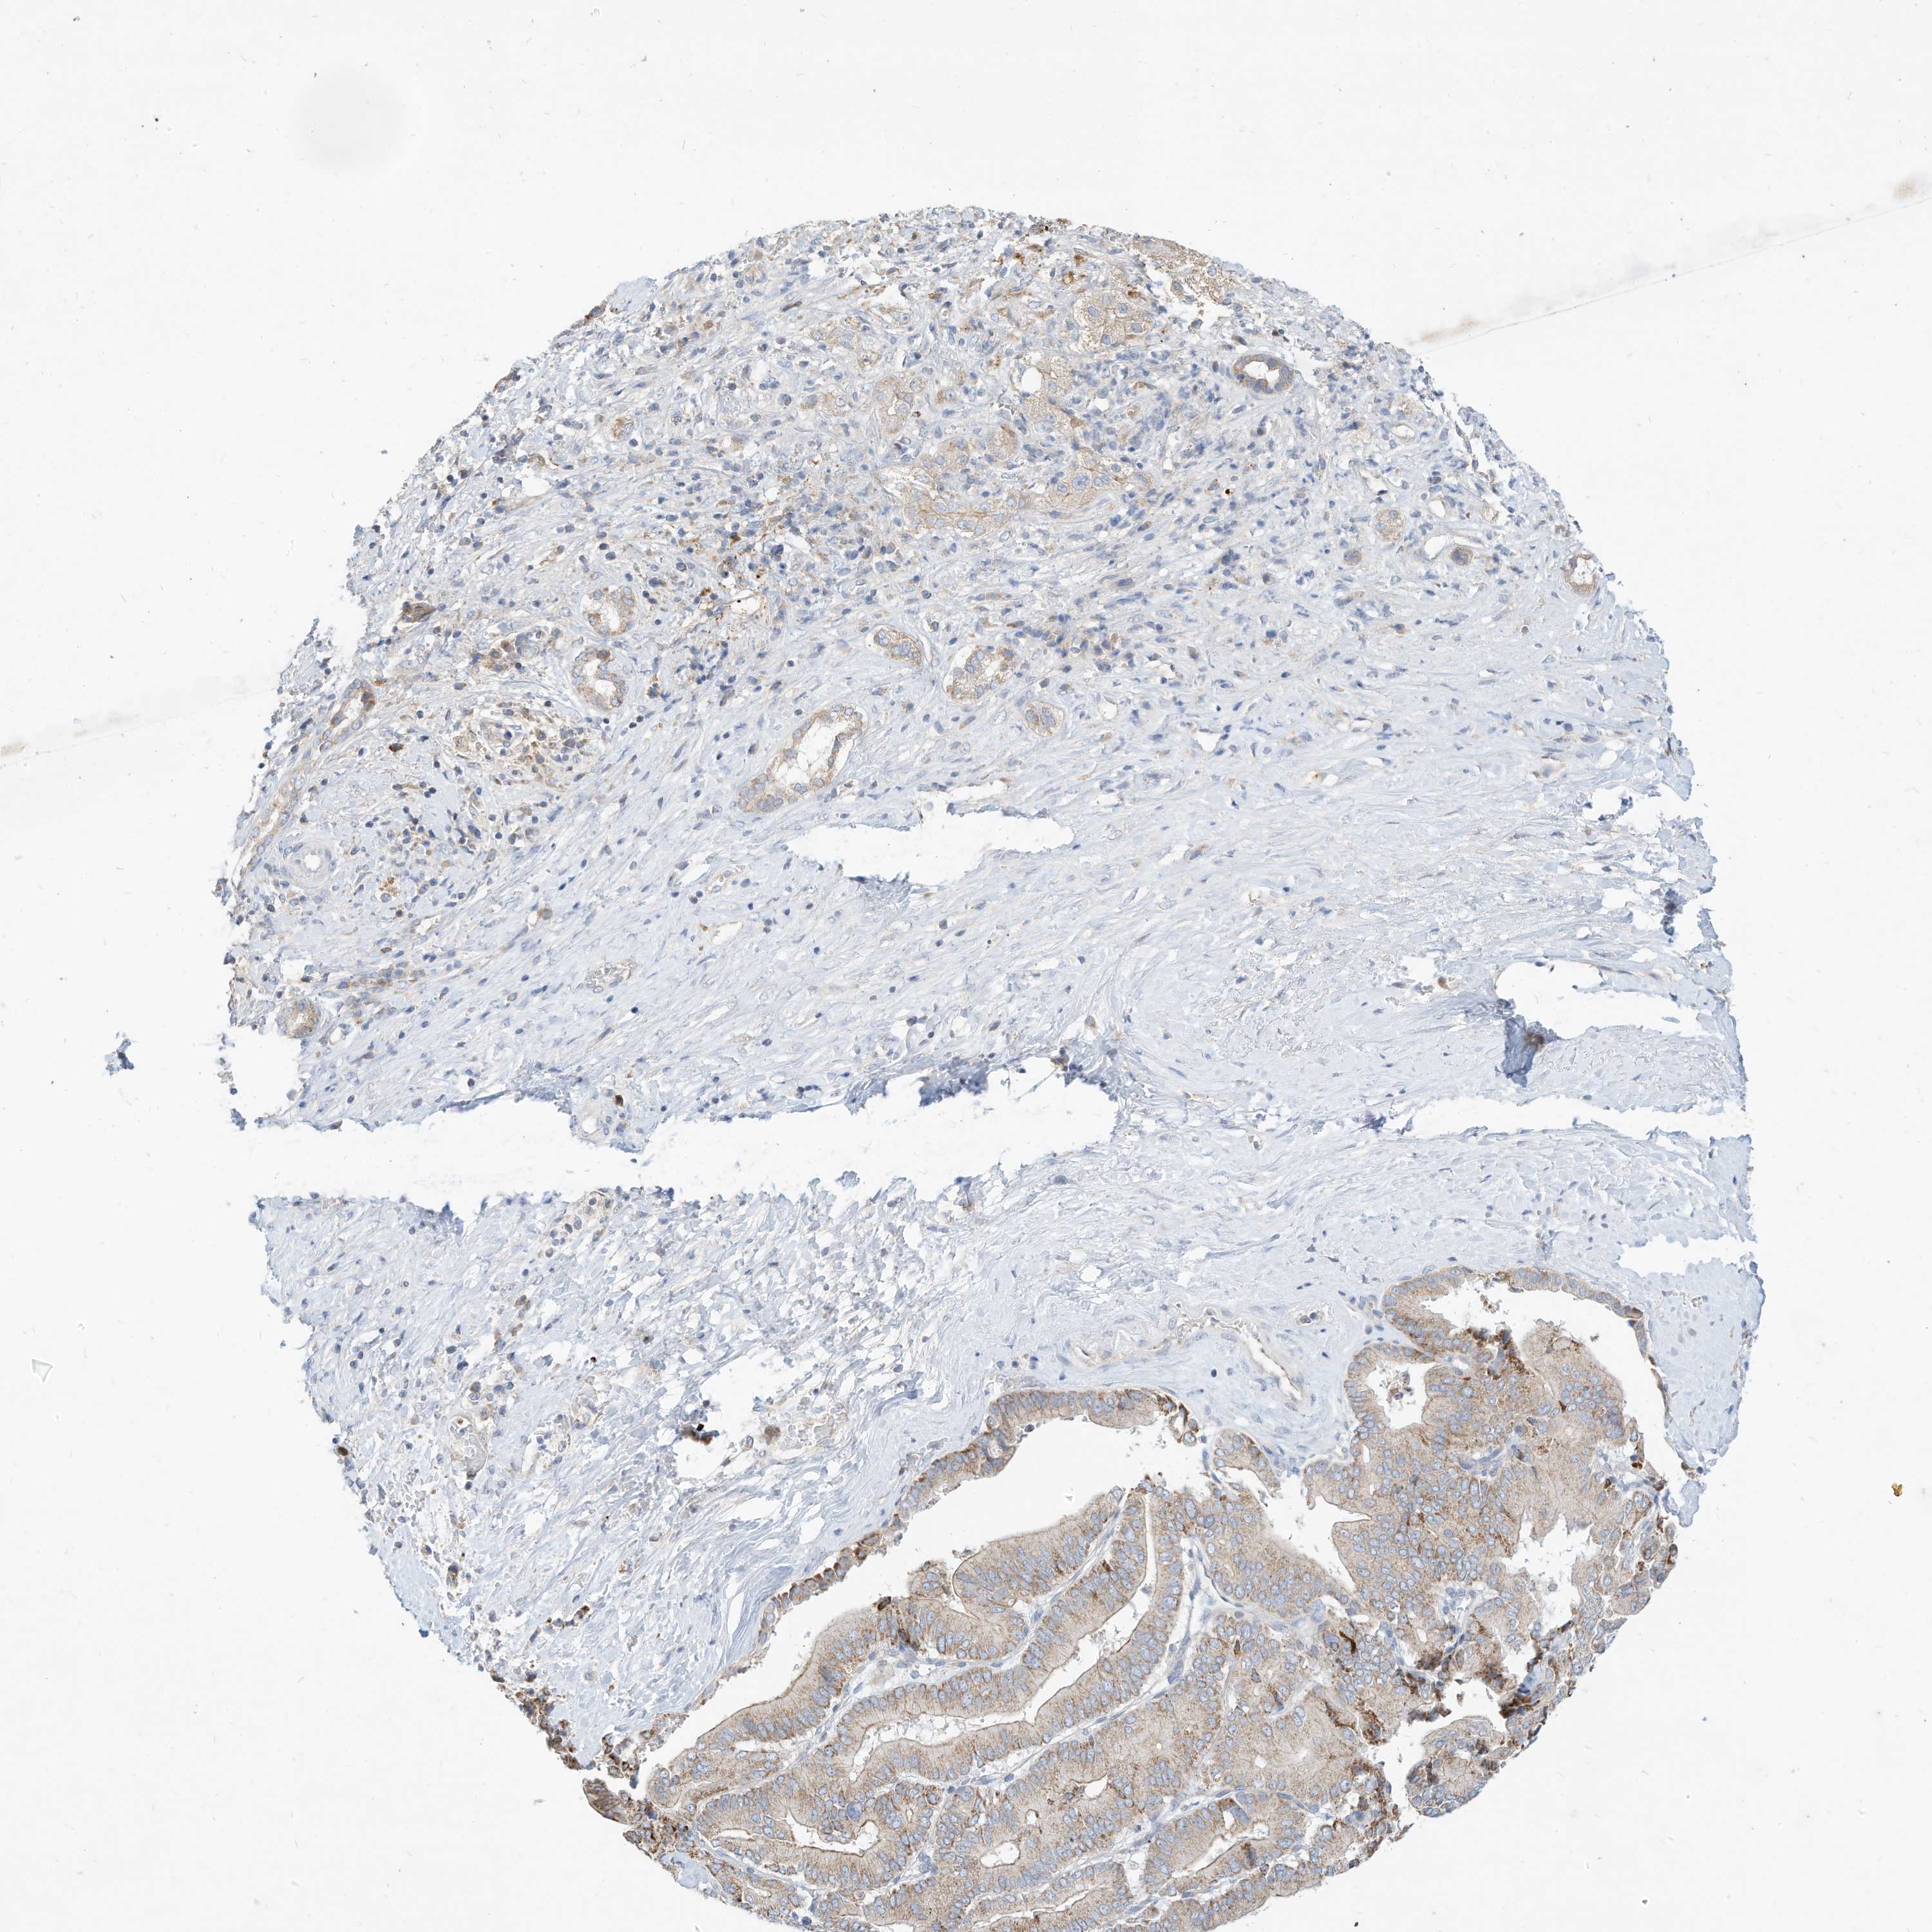

LIVER CANCER - Protein expressioni

A mouse-over function shows sample information and annotation data. Click on an image to view it in a full screen mode. Samples can be filtered based on level of antibody staining by selecting one or several of the following categories: high, medium, low and not detected. The assay and annotation is described here.

Note that samples used for immunohistochemistry by the Human Protein Atlas do not correspond to samples in the TCGA dataset.

Antibody stainingi

Antibody staining in the annotated cell types in the current human tissue is reported as not detected, low, medium, or high, based on conventional immunohistochemistry profiling in selected tissues. This score is based on the combination of the staining intensity and fraction of stained cells.

Each image is clickable and will lead to virtual microscopy that enables deeper exploration of all samples and also displays staining intensity scores, fraction scores and subcellular localization as well as patient and tissue information for each sample.

Antibody HPA030345

Staining

High

Medium

Low

Not detected

Intensity

Strong

Moderate

Weak

Negative

Quantity

>75%

75%-25%

<25%

None

Location

Nuclear

Cytoplasmic/membranous

Cytoplasmic/membranous,nuclear

Cholangiocarcinoma